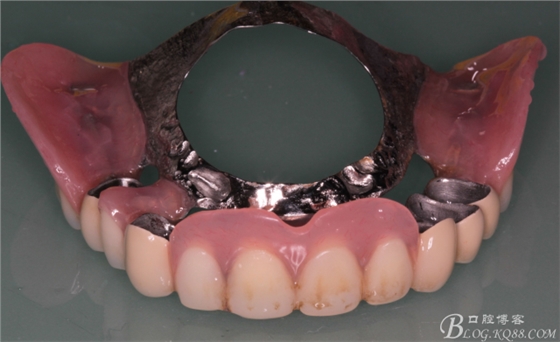

下頜由于44治療之后,松動(dòng)度改善不大,原來的咬合創(chuàng)傷比較大,不能承擔(dān)較大的(牙合)力,選擇覆蓋義齒,把它磨短平齊牙齦,

其他牙比較集中,選擇雙端球帽式附著體修復(fù)雙端游離缺失

修復(fù)后效果圖,